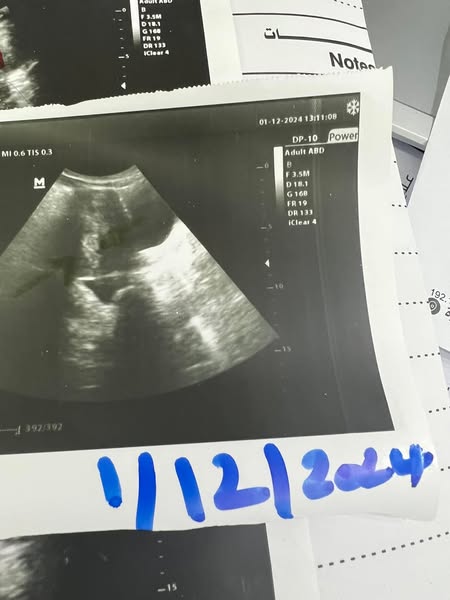

حالتنا اليوم كان مقرر لها قبل القدوم للمركز ازالة للرحم لوجود اورام ليفية متعددة ضخمة وانقطاع للدورة دام سنتين.

مع اختفاء للاورام الليفية واللحميات فى جدار الرحم.